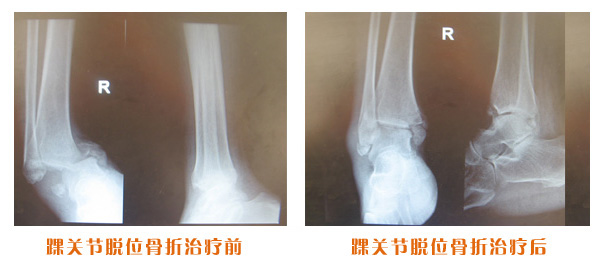

肥城市安駕莊梁氏骨科醫(yī)院是一所以梁氏手法正骨配合膏藥為特色的現(xiàn)代化??漆t(yī)院。

梁氏骨科術始創(chuàng)于清雍正年間,歷經(jīng)八代,至今已有三百年歷史。據(jù)1929年泰安縣志載“梁瑞圖先生,字增生,號蓮峰,安駕莊人,精岐黃并發(fā)明接骨,凡跌打車凡跌打車軋皮不破而碎骨者......【詳細】 |